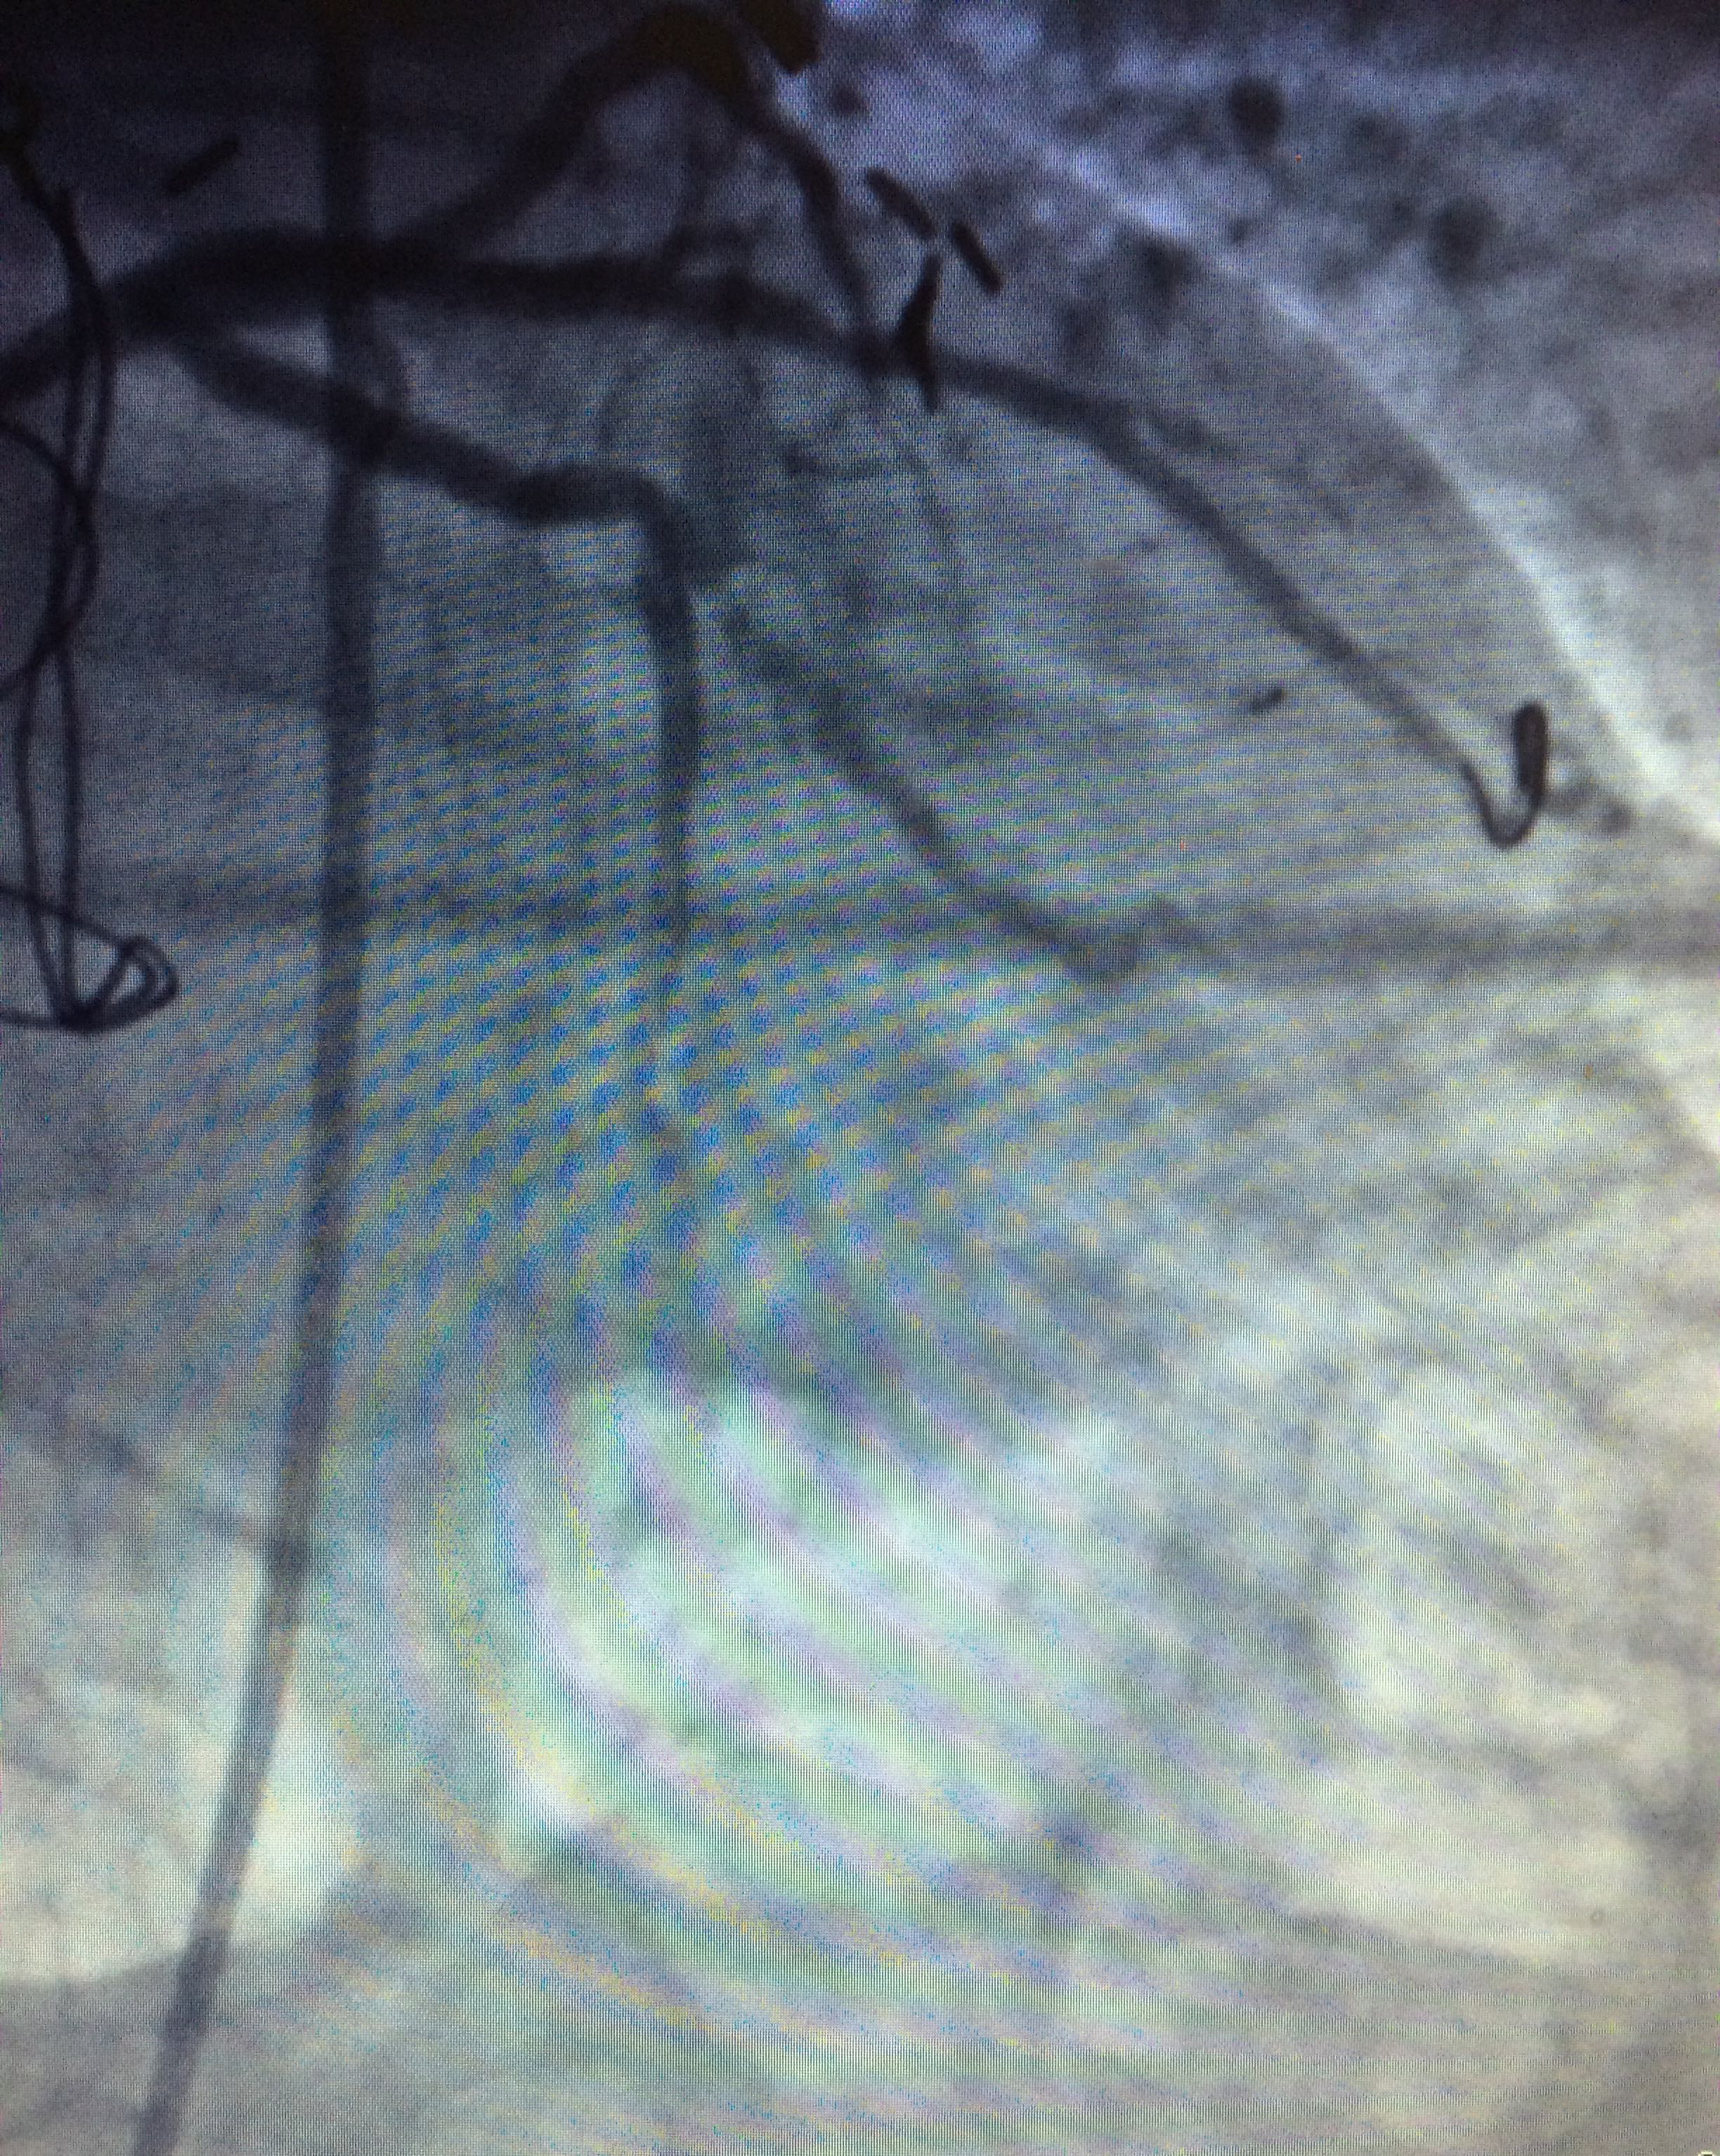

Figure 5 Five months later we decided to treat the ramus intermedius. We predilated the lesion with a 2.5x22mm Sprinter Balloon (Medtronic) to place a 2.5x22mm Endeavor stent inflated at 16 atm for 10 seconds obtaining good angiographic result.

Figure 6 Five months later we decided to treat the ramus intermedius. We predilated the lesion with a 2.5x22mm Sprinter Balloon (Medtronic) to place a 2.5x22mm Endeavor stent inflated at 16 atm for 10 seconds obtaining good angiographic result.

Five months later we decided to treat the ramus intermedius. We predilated the lesion with a 2.5x22mm Sprinter Balloon (Medtronic) to place a 2.5x22mm Endeavor stent inflated at 16 atm for 10seconds obtaining good angiographic result.